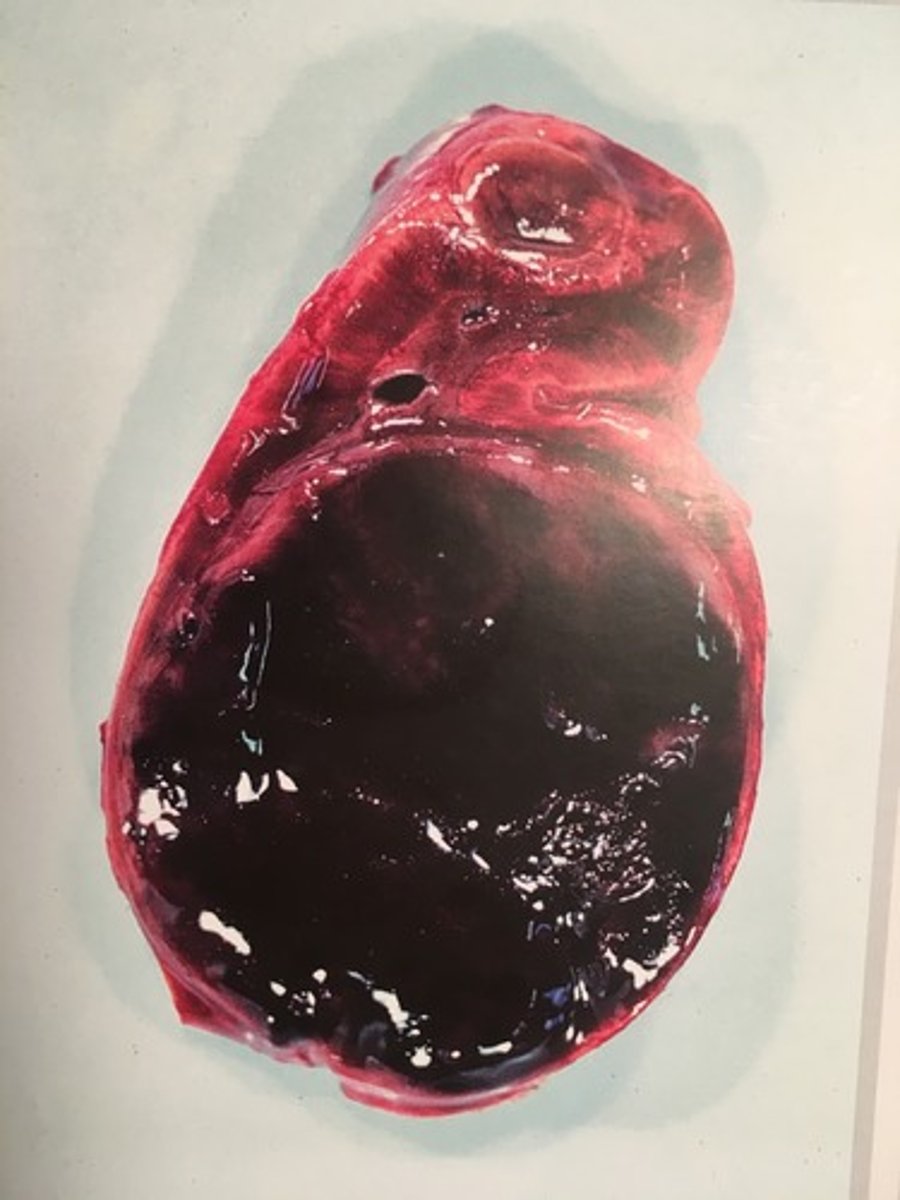

fæokromocytom

Adrenal kirtel (binyrer) fra hest, hvad er den patoanatomiske diagnose?

er tumorer opstået i de kromaffine celler i binyremarven, som producerer katecholaminerne adrenalin, noradrenalin og dopamin

Hvad er fæokromocytomer?